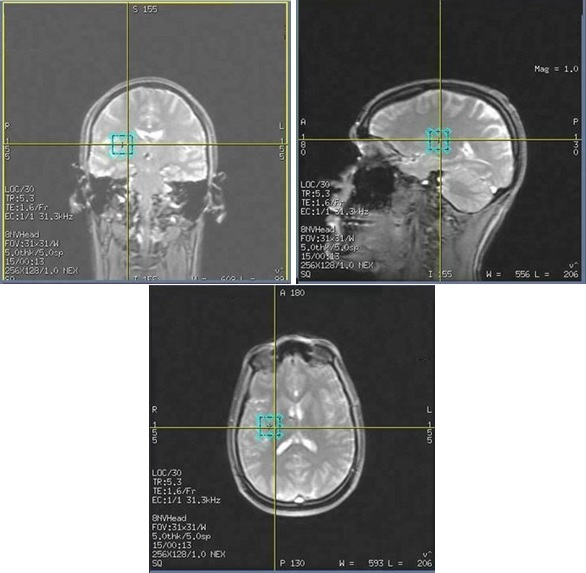

PROBE 2D CSI: acquire a scan

In order to display the localizer image in READY View, the center of each reference slice must be within 0.8 mm of each CSI slice. If a slice that meets this criterion does not exist in the selected reference series, READY View displays an error message, "Localizer loading failed, no matching image". Click OK to the error message. READY View launches, but an image does not display in the lower-left viewport. To avoid this problem, follow these guidelines when prescribing a 2D CSI scan.

Important: Do not save the 2D CSI protocol as an oblique plane. Save the protocol as an axial plane and then change the plane to oblique when you are viewing/editing the series.